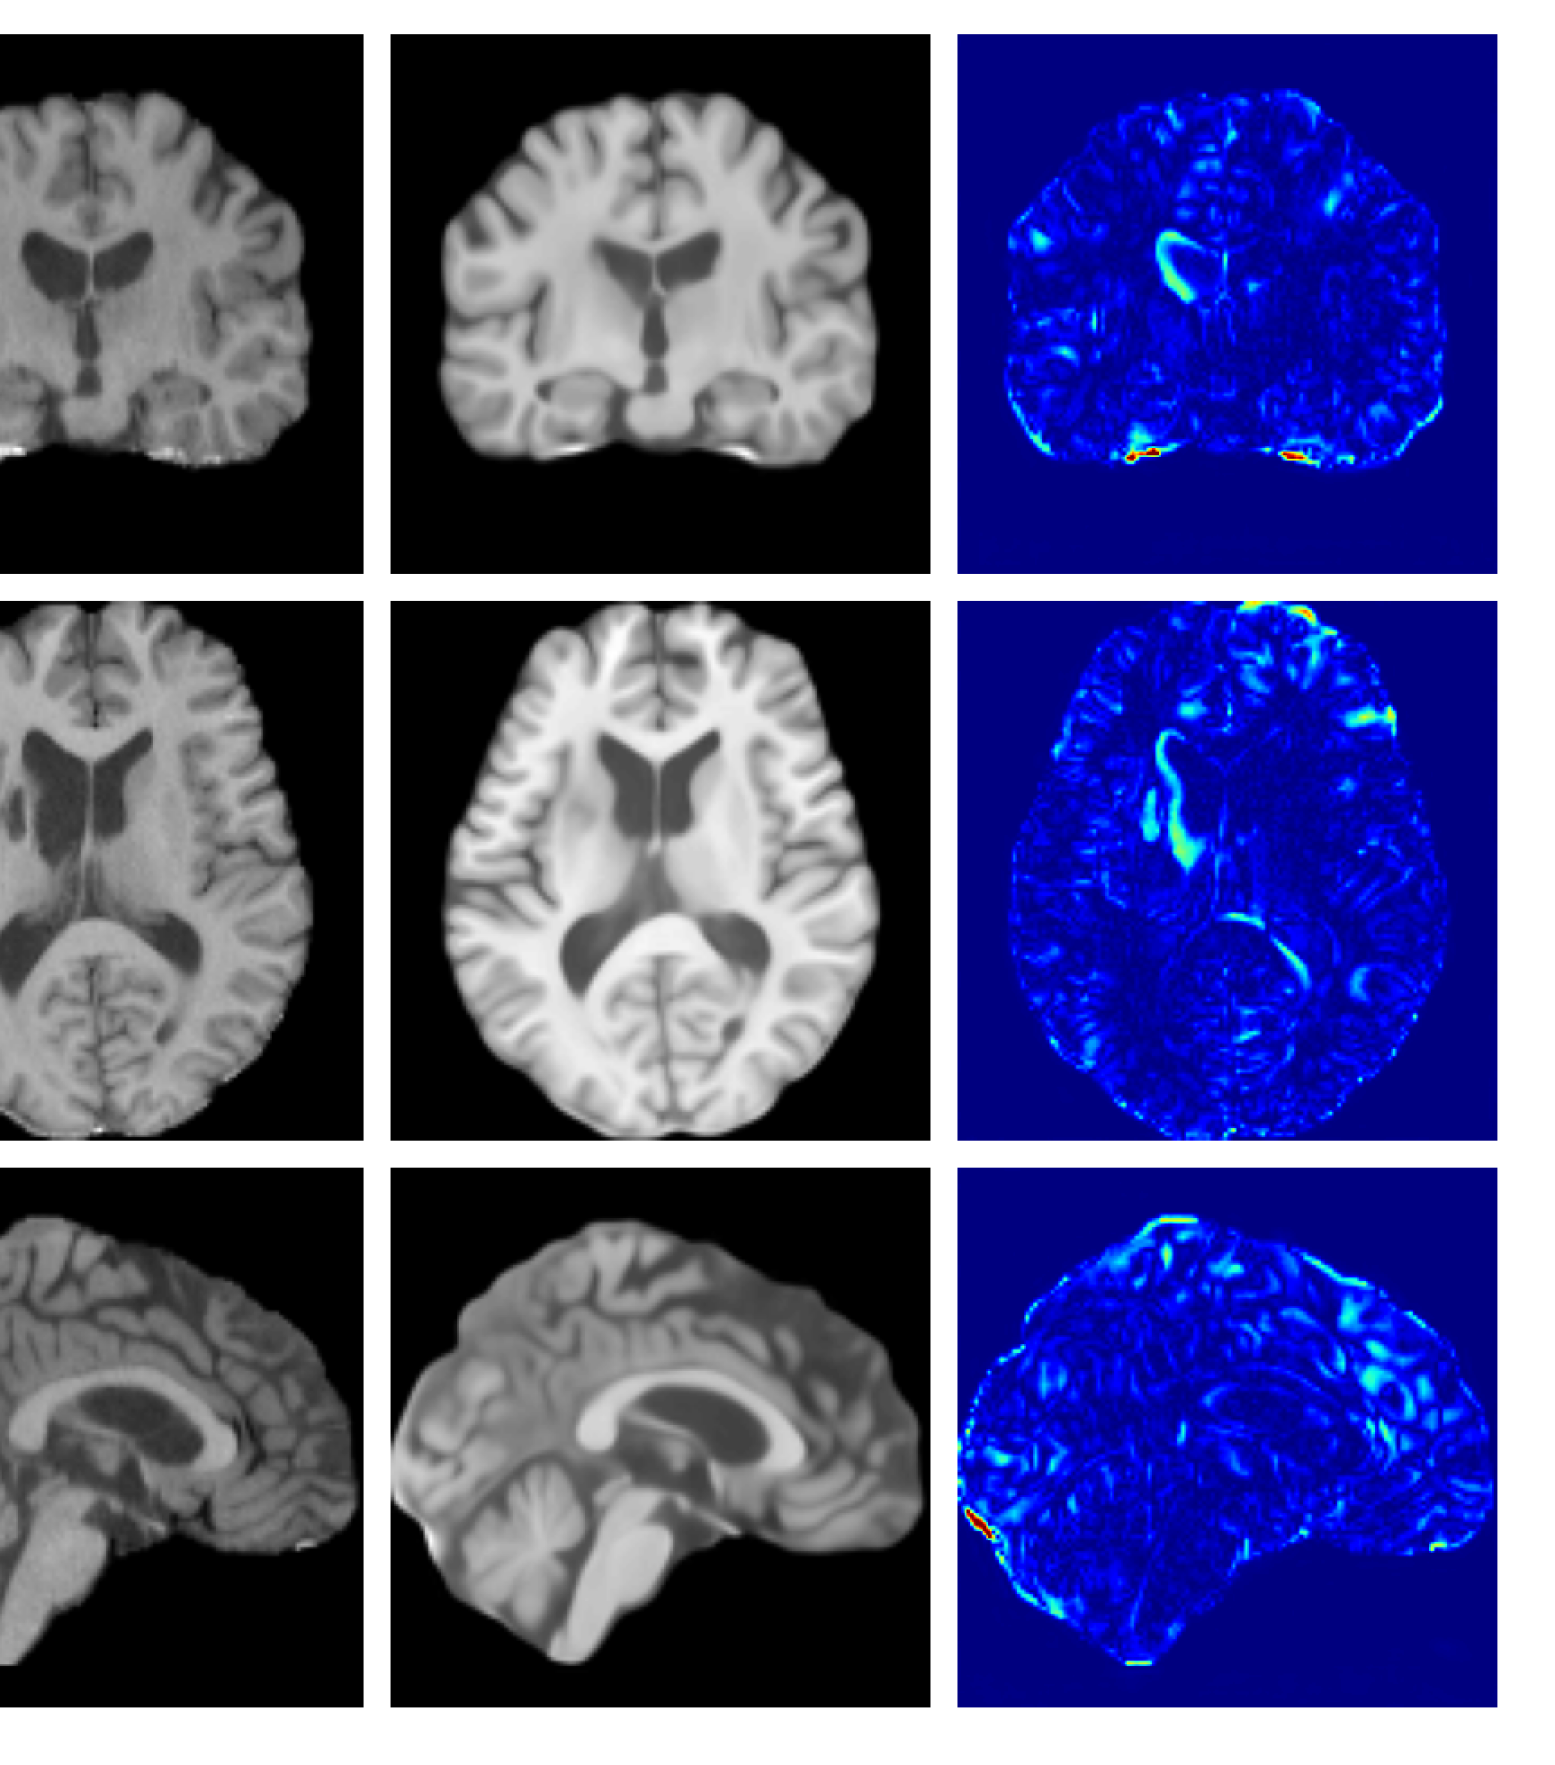

Figures 3 and 4, show example reconstructions and abnormality maps for a sample from the UKBB and UoTH datasets, respectively. Enlarged figures and additional example qualitative results for the ADNI dataset are available in the Supplementary. In Figure 3 we see that whilst all models are able to detect the lesion visible in the sagittal slice, the VAE, cVAE, LDM and LDM (TavgT_{avg}) produce very smooth outputs or lose defining characteristics and thus exhibit more false positives in healthy tissue. THOR and CADD provide the best results, with CADD better detecting white matter hypointensities (WMH). However, neither method fully inpaints all WMH, potentially due to presence of WMH in the healthy training set.

Figure 7 provides example reconstructions and anomaly maps for a healthy subject from the UK Biobank holdout test cohort.

Figure 7: Example healthy reconstructions and anomaly maps for a sample from the UK Biobank healthy test cohort. For a healthy subject, we should observe no regions highlighted in the anomaly map.